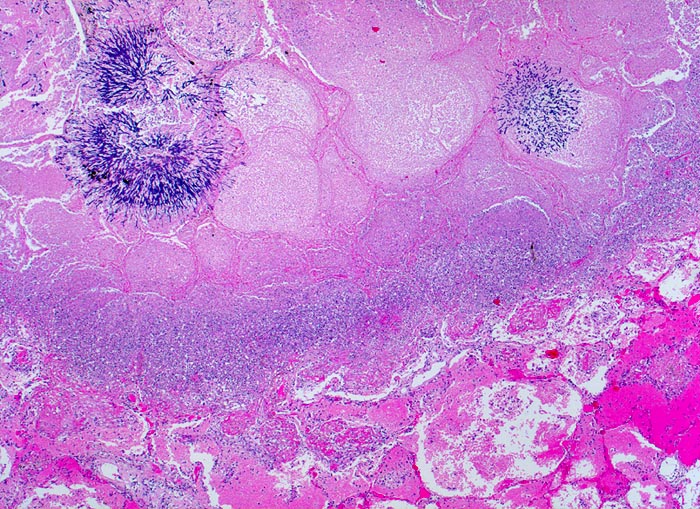

Aspergilluspneumonie

Zwei Pilzkolonien im Zentrum der Gewebsnekrose. Angrenzend an das Nekroseareal folgt ein Saum von zerfallenden neutrophilen Granulozyten (blau) und weiter aussen der hyperämische Randsaum mit den Fibrinexsudaten.

Seit 14 Monaten bekannte chronische lymphatische Leukämie behandelt mit Chemotherapie. Der Patient entwickelt unter Therapie eine Pneumonie und verstirbt an einer Pilzsepsis.